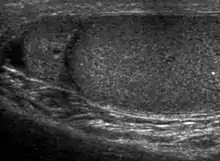

|  Sonography of a normal testis. The normal testis presents as a structure having homogeneous, medium level, granular echotexture. The mediastinum testis appears as the

hyperechoic region located at the periphery of the testis as seen in this figure. | |

The normal adult testis is an ovoid structure measuring 3 cm in anterior-posterior dimension, 2–4 cm in width, and 3–5 cm in length. The weight of each testis normally ranges from 12.5 to 19 g. Both the sizes and weights of the testes normally decrease with age. At ultrasound, the normal testis has a homogeneous, medium-level, granular echotexture. The testicle is surrounded by a dense white fibrous capsule, the tunica albuginea, which is often not visualized in the absence of intrascrotal fluid. However, the tunica is often seen as an echogenic structure where it invaginates into the testis to form the mediastinum testis. In the testis, the seminiferous tubules converge to form the rete testes, which is located in the mediastinum testis. The rete testis connects to the epididymal head via the efferent ductules. The epididymis is located posterolateral to the testis and measures 6–7 cm in length. At sonography, the epididymis is normally iso- or slightly hyperechoic to the normal testis and its echo texture may be coarser. The head is the largest and most easily identified portion of the epididymis. It is located superolateral to the upper pole of the testicle and is often seen on paramedian views of the testis. The normal epididymal body and tail are smaller and more variable in position.